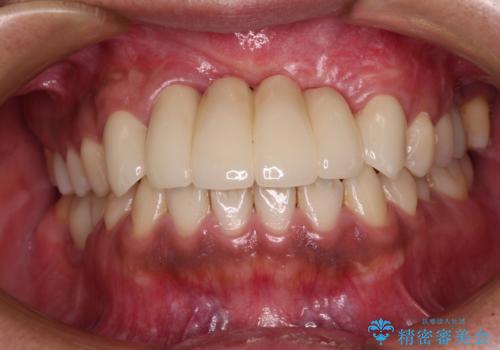

- 笑うときに目立つ銀歯を白くしたいとのことで来院された患者様です。

奥歯ではありますが、以前抜歯矯正をされているので前の方へ移動しており、非常に目立っていました。

仮歯に替えた上で、速やかにオールセラミッククラウンにて補綴治療を行うこととしました。

銀歯を外したところ、土台にほとんどむし歯はなかったため、土台のやり替えを行うことなく、セラミッククラウンを装着しました。